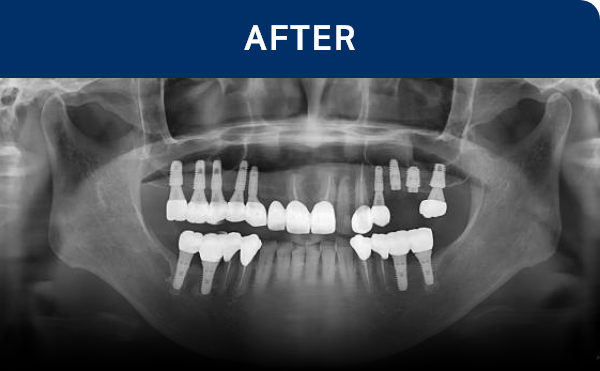

전후가 명확한 결과, 그 결과가

곧 신길플란트치과의 신뢰입니다.

임플란트는 정확한 진단과 계획을 기반으로

여러 단계를 거쳐 진행되는 치료입니다.

환자분의 구강 상태에 맞춰

단계별로 안전하게 진행됩니다.